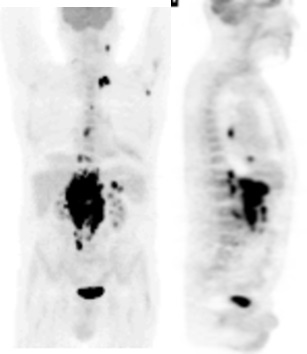

Imagerie évaluation de la réponse :

Evaluation réalisée 3 mois après autogreffe par scanner et TEP-FDG confirmait la rémission complète.

Classement en fin de traitement : rémission complète